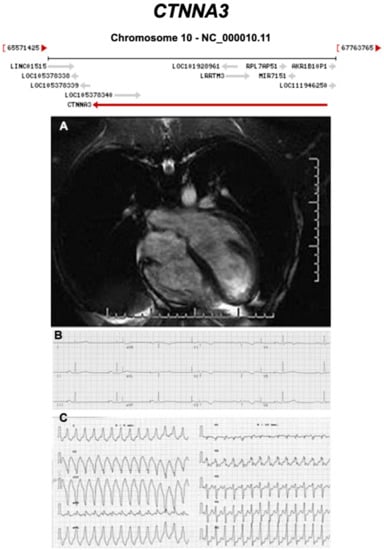

3.2.7. Catenin Alpha 3 (CTNNA3) (Encoded by CTNNA3)

- van Hengel, J.; Calore, M.; Bauce, B.; Dazzo, E.; Mazzotti, E.; De Bortoli, M.; Lorenzon, A.; Li Mura, I.E.A.; Beffagna, G.; Rigato, I.; et al. Mutations in the area composita protein αT-catenin are associated with arrhythmogenic right ventricular cardiomyopathy. Eur. Heart J. 2013, 34, 201–210. [Google Scholar] [CrossRef] [PubMed]

- Goossens, S.; Janssens, B.; Bonné, S.; De Rycke, R.; Braet, F.; van Hengel, J.; van Roy, F. A unique and specific interaction between alphaT-catenin and plakophilin-2 in the area composita, the mixed-type junctional structure of cardiac intercalated discs. J. Cell Sci. 2007, 120, 2126–2136. [Google Scholar] [CrossRef]

- Li, J.; Goossens, S.; van Hengel, J.; Gao, E.; Cheng, L.; Tyberghein, K.; Shang, X.; De Rycke, R.; van Roy, F.; Radice, G.L. Loss of alphaT-catenin alters the hybrid adhering junctions in the heart and leads to dilated cardiomyopathy and ventricular arrhythmia following acute ischemia. J. Cell Sci. 2012, 125, 1058–1067. [Google Scholar] [CrossRef] [PubMed]

| CTNNA3 | Intercalated Disc | <1% | AD | RV, BIV | ARVC13 | 10q21.3; 27 | Low penetrance | Limited for ARVC |